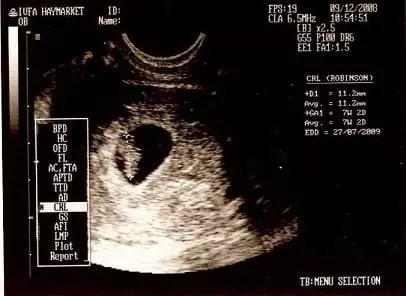

通过孕囊形状看男女,不是简单地看B超单上的形状,而是根据孕囊的三边数据去想象它的形状。

很多妈妈只是简单的根据B超影像是否长或圆来判断男女,这样误判率是很高的。

1、仅限8周之前的B超单

孕囊要看早期形状,40-50天左右是最准的,如果是9周以后的数据准确性就很低了,妈妈们快翻翻早期的B超单。

2、需要有孕囊的3个边长数据

很多妈妈的B超单上只有两个数据,比如4.0cm*2.6cm,这只是横截面的数据,不能用来看男女,很多妈妈看错就是这个原因。只有3个数的数据才能看,比如4.0cm*3.8cm*2.6cm。

根据前辈们的经验,长条形孕囊是男生,反映在数据上就是,其中两条边长要是第三条边长的两倍以上,比如4.0cm*3.8cm*1.9,这种两条长边接近,正好是第三条边2倍的,是标准男宝。比如4.0com*3.2.com*1.2cm,这种一条边特别短的80%是男宝。这些都可以想象出来因为有一条边特别短,所以孕囊肯定是细长型的。

圆形孕囊是女生,反映在数据上就是,三条边长差不多,或三条边长成等差数列,长边没有短边两倍的,比如4.0cm*3.3cm*2.7cm或2.9cm*1.8cm*1.8cm,这些都是女孩。

有的妈妈B超单上只有两个数是4.0cm*2.0cm,就觉得长边是短边的2倍肯定是男孩,很多最后都验证错了,因为中间的边长可能是3.0cm,就是标准的等差数列,其实是女孩。所以一定不能只看两个数的B超单!

有的人数据是2.7*3.6*1.8,第一个数字不是最大值怎么看,没关系,按照从高到低再排列成3.6*2.7*1.8这样看就行。当然也有一些妈妈的数值不是很明显符合以上特征的,那就是男女都有几率了。